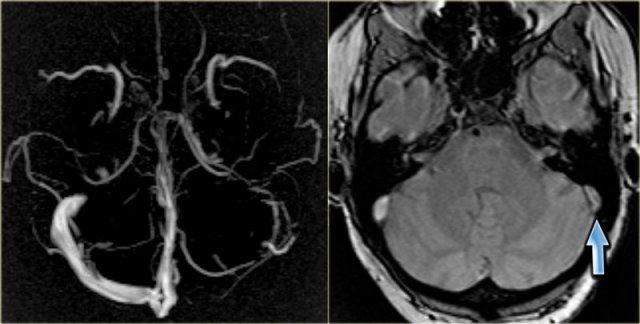

On the left a transverse MIP of phase-contrast images.

To differentiate whether there is a hypoplastic transverse sinus or thrombosed sinus, you need to look at the source images.

On the source image on the right you can see that there is no hypoplasia (blue arrow).

In this case there thrombosis of the left transverse sinus.

On the left a T2-weighted image with normal flow void in the right sigmoid sinus and jugular vein (blue arrow).

On the left there is abnormal high signal as a result of thrombosis (red arrow).